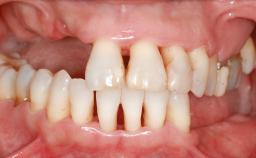

A woman in her mid-fifties was referred by a dental student for dental implant placement. Both posterior segments of the mandible had been edentulous for more than 4 years, the only residual tooth being the right lower first premolar. The patient had used a removable partial denture but was not entirely satisfied with its function. The clinical examination revealed a sharp edentulous ridge in both posterior segments of the mandible, and the patient was told that it would not be possible to insert implants into this thin edentulous ridge without significant augmentation of the alveolar ridge. Her medical history revealed no significant findings and no underlying disease that might have complicated surgical procedures. During the presurgical examination, the patient reported that she was a little apprehensive about bone grafting. After being informed about the surgical procedures and potential postoperative complications, she accepted the proposed surgical plan of bone grafting and subsequent placement of implants.

Prosthesis Type FDP

Defining Characteristics Up to three missing teeth to be replaced with an implant-borne restoration or restorations